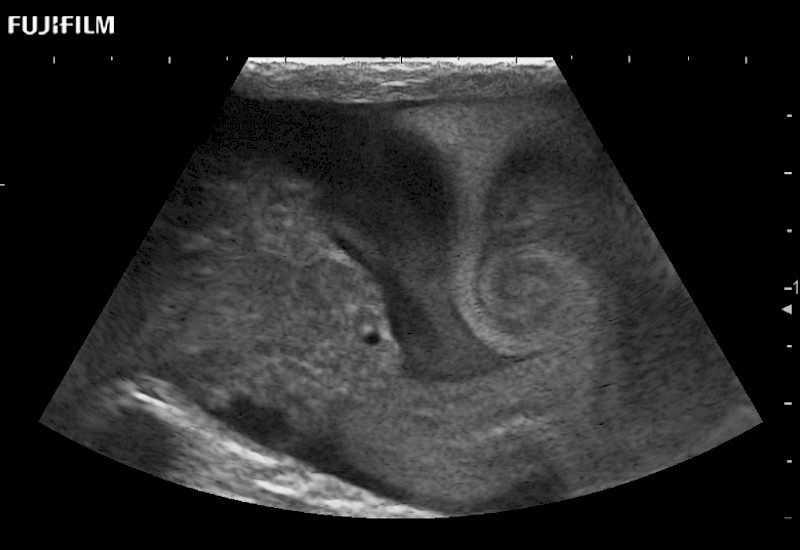

Curved array 4-way laparoscopic transducer for better visualization of targeted lesions.

Exclusive linear array robotic surgery transducer.